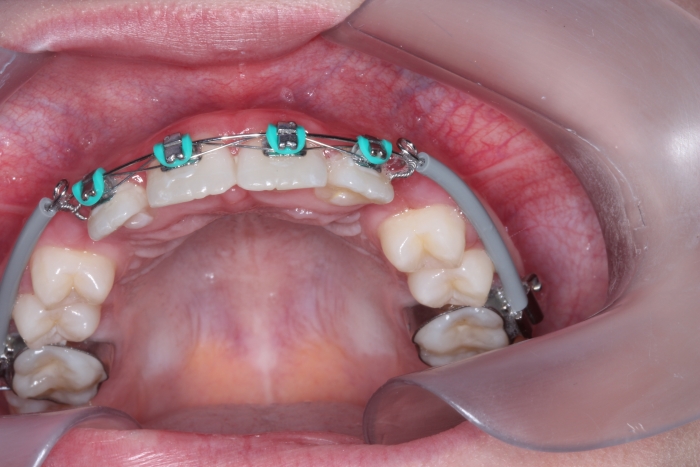

Dentes em tracionamento